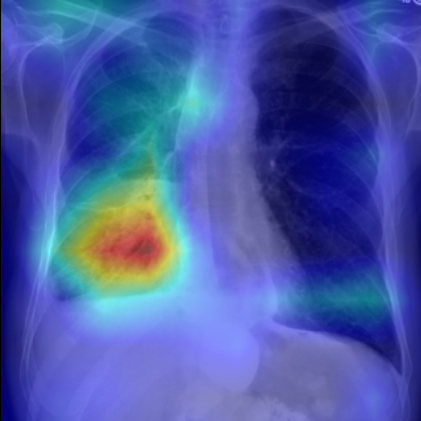

Refer to caption

Figure 5: Visualization of attention map in PLAN on MS-CXR. The red boxes indicate the corresponding ground truth of grounding. Highlighted pixels represent higher activation weights correlating specific words with regions in the image.

IV-B1 Phrase Grounding

Phrase grounding associates textual phrases (e.g., disease descriptions or anatomical terms) with corresponding regions in medical images, offering precise diagnostic insights and enhancing model interpretability. Table II presents the phrase grounding results on the MS-CXR dataset. Using the Contrast-to-Noise Ratio (CNR) [27] as the evaluation metric, PLAN achieved the highest CNR across eight disease categories, outperforming MGCA and PRIOR. Heatmaps generated with Grad-CAM (Figure 4) further illustrate PLAN’s ability to accurately localize lesion sites and align disease-related phrases with image regions. Additional comparisons with baseline methods can be found in Figure 5. These findings highlight PLAN’s superior precision and interpretability in phrase grounding tasks.